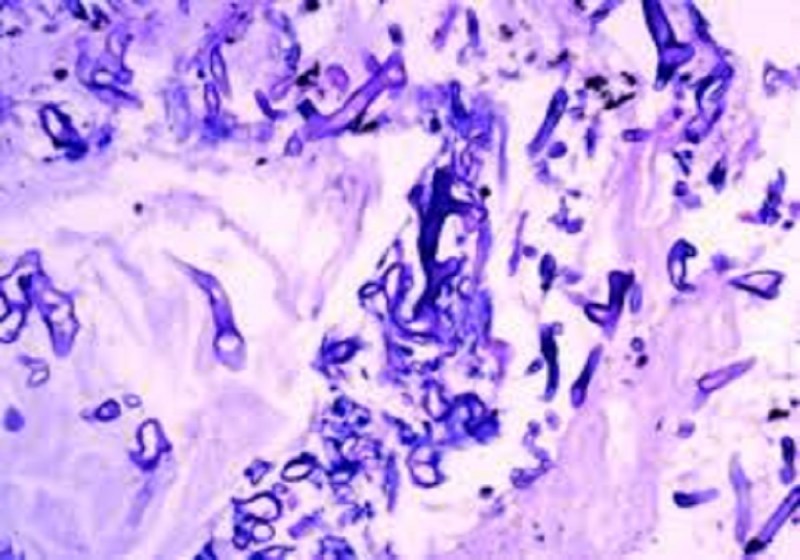

कानपुर. अभी तक कोरोना संक्रमण (Corona Virus) को लेकर लोग जूझ रहे थे, लेकिन अब संक्रमण के साथ म्यूकोर माइकोसिस (Mucor Mycosis) का अटैक भी मरीजों में देखने को मिल रहा है, जो मरीजों के लिए घातक साबित हो रहा है। कानपुर में म्युकोर माइकोसिस के संक्रमित मरीज (Mucor Mycosis Patients) अस्पताल में पहुंचे। यहां तक कि इसके प्रकोप से दो मरीजों की मौत हो चुकी है। दोनों के मौत की वजह के पीछे कोरोना संक्रमण के साथ म्यूकोर माइकोसिस का संक्रमण भी बताया गया है। कानपुर के बर्रा निवासी एक 49 वर्षीय महिला का केस सामने आया हैं, जो मैटरनिटी विंग में भर्ती थीं।

चिकित्सक के मुताबिक उनकी आंखों में सूजन और आंखो का रंग लाल था। साथ ही स्पाइन पर समस्या थी। फेफड़े में गम्भीर रूप से जकड़न थी। इन लक्षणों के आधार पर डॉक्टरों ने म्यूकोरमाइकोसिस की पुष्टि की है। मैटरनिटी विंग में भर्ती मरीज को तीन डॉक्टर देख रहे थे, जिसमें दो मेडिसिन विभाग के थे और एक नेत्र रोग विशेषज्ञ थे। हालांकि डॉक्टरों ने बताया है कि सभी जांच नहीं हो सकी क्योंकि मरीज का ऑक्सीजन लेवल बहुत कम था। उससे उसकी मौत हो गई। उधर वार्ड नंबर तीन में भर्ती 55 वर्षीय पुरुष की आंखों में इतनी सूजन आ गई थी कि आंखें बंद हो गई थीं।

मेडिकल कॉलेज के न्यूरोलॉजिस्ट प्रो. आलोक वर्मा का कहना है कि मरीज उनके अंडर में भर्ती था। उसके चेहरे पर भी सूजन थी। उसके लक्षण अन्य मरीजों से अलग थे। लक्षणों के आधार पर म्यूकोरमाइकोसिस की डायग्नोसिस की गई है। मरीज में संक्रमण जबरदस्त था। ब्रेन में सूजन आ गई थी। फंगस के असर से फेफड़े बिल्कुल फेल हो गए थे। जांच कराने का समय नहीं मिला। इस बीच मरीज ने दम तोड़ दिया। प्रो. आलोक कुमार के मुताबिक दो केस अभी तक मेडिकल कॉलेज में रिपोर्ट हुए हैं।